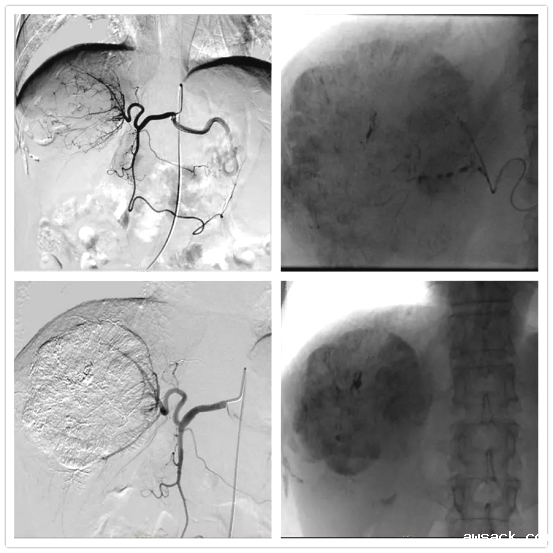

经动脉灌注化疗栓塞术(TACE,transcatheter arterial chemoembolization)

将导管选择性或超选择性插入到肿瘤供血靶动脉后,以适当的速度注入适量的栓塞剂,使靶动脉闭塞,引起肿瘤组织的缺血坏死。使用抗癌药物或药物联合微粒、微球进行栓塞可起到化疗性栓塞的作用,称之为TACE(transcatheter arterial chemoembolization)。最多用于肝癌的治疗,包括:肝动脉插管化疗栓塞,或肝动脉插管化疗灌注。